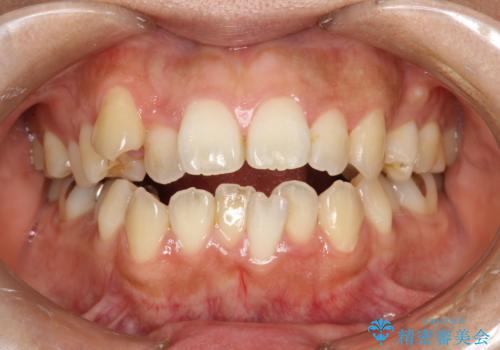

歯科矯正前のPMTC

治療症例の内容

- 20代女性

- 1日

- 1回

- 矯正前にしっかりとクリーニングを行いたいとのことで来院されました。PMTC30分コースを行いました。

- 5千円+tax費用は治療当時の料金となります

プラーク(細菌の塊)や歯石がたまると歯の表面はザラつきいてきます。そのザラつきは歯周病や虫歯菌の棲家となります。そのまま放置すると、歯肉が腫れてきたり、歯肉から出血したり、口臭が強くでたりします。とくに歯肉の境目は、歯磨きで汚れを除去することが難しく、プラーク(細菌の塊)や歯石が溜まりやすい場所です。

歯並が、がたついている場合はなおさら汚れが溜まりやすいです。矯正治療前や定期的にPMTCをすることで、矯正治療中の歯肉トラブルを防ぐことにつながります。